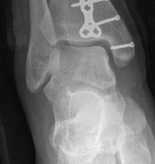

Definitive Lag Screw and Plate Fixation

The definitive fixation sequence is critical to achieving absolute stability:

1. Independent Lag Screws: If the fracture morphology permits, independent lag screws are placed perpendicular to the fracture plane. The standard sequence is utilized: 4.5mm gliding hole in the near cortex, insertion of the drill sleeve, 3.2mm thread hole in the far cortex, countersinking, measuring, tapping, and screw insertion.

2. Plate Application: A pre-contoured anatomic locking plate or a standard buttress plate (e.g., L-buttress or T-plate) is applied to the lateral cortex. The plate must sit flush against the bone at the apex of the fracture.

3. Diaphyseal Fixation First: To achieve the buttress effect, the plate is first secured to the intact distal diaphyseal segment using cortical screws. If the plate is slightly under-contoured, tightening these diaphyseal screws will drive the proximal portion of the plate into the metaphyseal flare, compressing the articular fragment.

4. Periarticular Screws: Subchondral "rafting" screws are then inserted through the proximal holes of the plate. These screws support the elevated articular cartilage and neutralize any remaining forces. In modern osteosynthesis, locking screws are frequently utilized in the periarticular segment to create a fixed-angle construct, which is particularly beneficial in osteopenic bone.